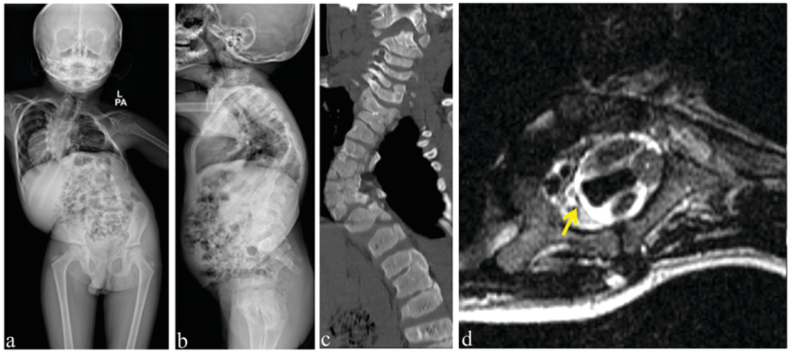

Fig. 3.

Showing calcified ligamentous structures around the neural elements in the spinal canal: (a–b) Sagittal CT scan and MRI showing thick OPLL mass behind C6 vertebral body occupying about half of the spinal canal with cord signal changes; (c) Mid-sagittal CT scan image of thoracic spine showing ossified ligamentum flavum at multiple levels; (d) Axial CT scan images showing significant narrowing of the spinal canal; (e–f) Calcified L4-5, L5-S1 disc prolapsed. In all these patients there are high chances of dural tear during decompression.

In our study, the surgical step which resulted in the most number of durotomies was during the removal of lamina and kerrison rongeur was the most common instrument that resulted in injury (54.5%). In patients with chronic lumbar canal stenosis, loss of epidural fat and thinning of the dura ensues with adhesions to the surrounding structures.11 This can also lead to the thecal sac getting trapped in while using the Kerrison rongeur. Hence it is essential to maintain the perpendicular placement of the kerrison over the dura and visualise the foot plate of kerrison at all times while performing decompression. Also, a kerrison rongeur with a smaller foot plate can result in entrapment of this thinned out dura by point contact compared to a broader foot plate. The surgeon must be aware of all these technique related aspects while using the kerrison rongeur. Similarly in patients with ossified ligamentum flavum (Fig. 3) there is a higher incidence of dural injury (3 patients in our study) especially when there is associated dural ossification. Epstein et al. in a study of 110 geriatric patients undergoing multilevel laminectomy and non-instrumented fusions found a close association of dural tear with calcified ligamentum flavum extending to the dura and with synovial cysts.12 Therefore such patients warrant a close study of preoperative imaging for the surgeon to exercise additional care and restraint during decompression at the affected levels.13 One of our patients with congenital thoracic kyphoscoliosis, had a dural tear during laminectomy at the apex of the deformity. In these complex spinal deformities, the dura will be in close proximity to the bony elements especially on the concave side of the deformity (Fig. 5). Also, adhesions at the apex around the thecal sac could be present, which further increases the risk of dural tears in these patients during decompression of the spinal cord.